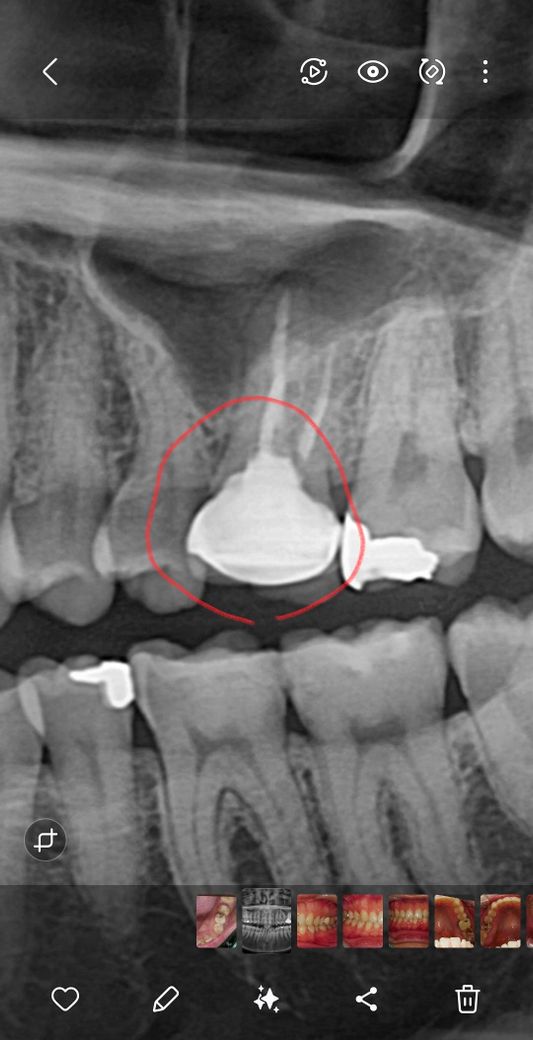

10년전 크라운치료 한 치아인데 뿌리쪽에 뭐가 되있는건가요?

보통 크라운 파노라마보면 보철물과 잇몸부위경계부위가 일직선? 으로 나오던데 뿌리 쪽까지 크라운보철물 형태가 보여서 저 부분이 무엇인지 궁금합니다

신경치료를 하고 크라운을 씌우셨네요. 신경치료는 치아뿌리쪽의 신경을 제거하는 치료지만, 그 뿌리부분으로 진입하기 위해서는 치아머리부분부터 구멍을 뚫고 들어가야합니다. 그 구멍을 차후에 치과코어재료로 메꾼것이 겉에 씌운 크라운과 겹쳐져서 보이는 것입니다.

말씀하신 부위는 크라운이 아닌 내부 충전물입니다. 신경치료를 하고 나서 해당 부분을 다시 채워 넣게 되는데 이것이 하얗게 보일 수 있습니다. 또한 크라운을 하게 되면 모든 경우가 일직선이 아니며 잇몸 모양에 따라 약간 둥글게 나올 수 있습니다.

신경치료를 마무리하고 신경치료를 한부위를 충전제로 충전을 하게 되면 해당부위가 방사선 불투과성이 되기 때문에 하얀색으로 보이게 됩니다.

크라운 전 신경치료를 한 것입니다. 신경치료 마무리 단계에서 깨끗이 소독한 신경관을 치과용 재료로 채워넣은 것이고 방사선 불투과성 재료이므로 저렇게 엑스레이상에서 보입니다.

치아 뿌리끝에 염증이 약간 잇지만 크게 문제가 되는건 아닙니다. 증상이 없다면 계속 사용하셔도크게 문제가 되지 않습니다.